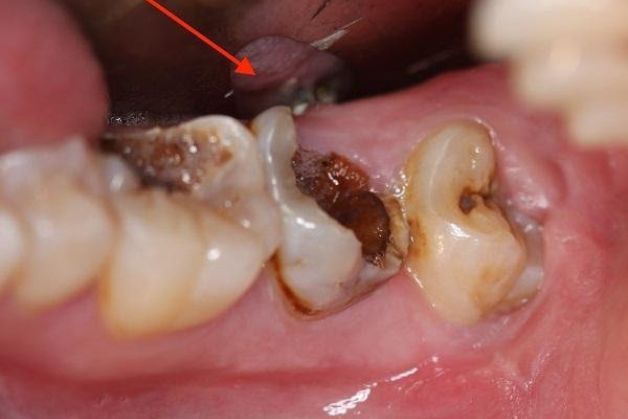

Răng số 7 bị sâu nặng

Răng số 7 bị sâu nặng là nguyên nhân phổ biến nhất dẫn đến việc nhổ bỏ. Khi sâu răng đã lan rộng tới tủy răng và không còn khả năng chữa trị, bác sĩ thường khuyên nên thực hiện nhổ răng nhằm tránh các biến chứng nguy hiểm.

Nếu bạn cảm thấy đau nhức hoặc có triệu chứng như sưng lợi, hãy nhanh chóng đến nha sĩ để kiểm tra tình trạng của răng số 7.

Hình ảnh răng số 7 bị sâu nặng